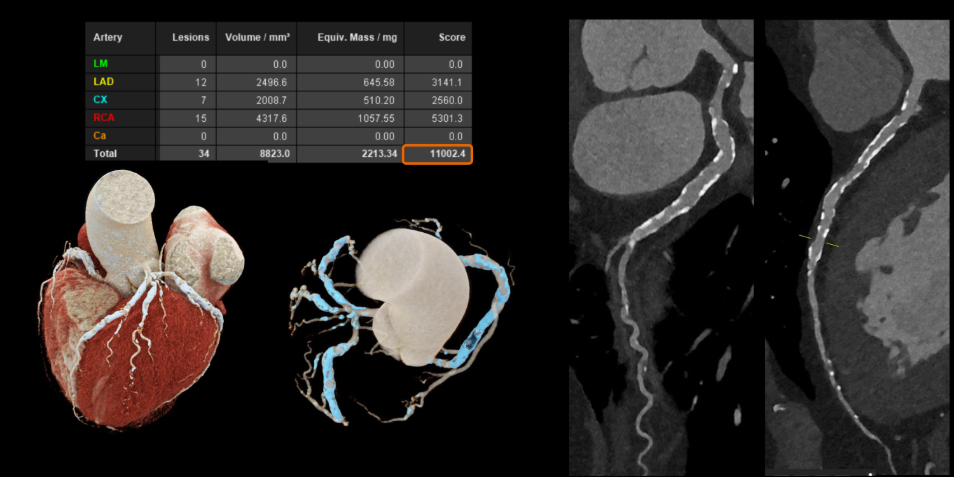

Với các bệnh tim mạch, đặc biệt ở những bệnh nhân đã đặt stent hoặc có mạch vành bị vôi hóa nặng – vốn là những trường hợp khó đánh giá bằng CT thông thường. Công nghệ này cho phép hình ảnh rõ ràng hơn đáng kể. Nhờ đó, bác sĩ có thể quan sát chính xác lòng mạch và các mảng xơ vữa, ngay cả khi bệnh nhân có nhịp tim cao hoặc loạn nhịp mà không cần sử dụng thêm thuốc hỗ trợ.

Hình ảnh mạch vành cho thấy độ rõ cao hơn, giảm nhiễu và giúp đánh giá chính xác hơn (Nguồn: Siemens Healthineers)